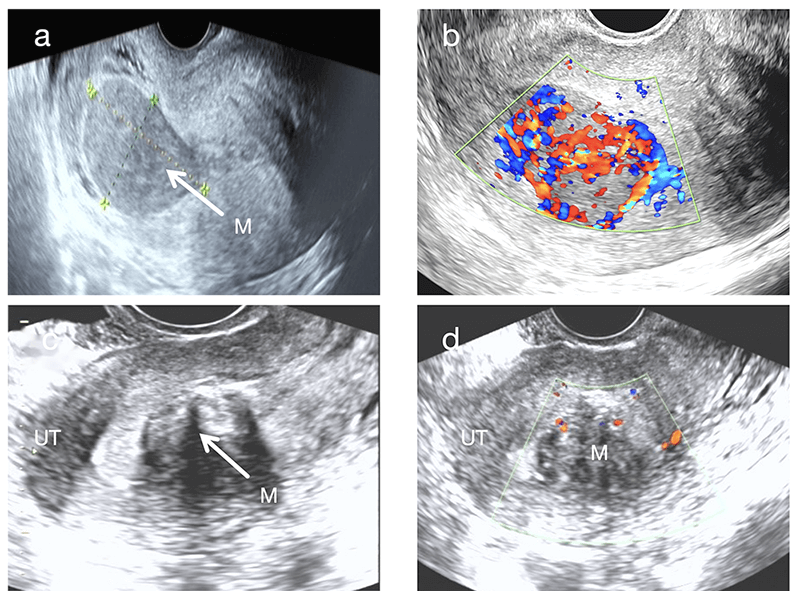

From the perspective of tumor size and growth characteristics, UIMT masses are often relatively large. The median maximum diameter of UIMT masses in this study was 6.9 cm, slightly larger than the 5 cm reported by Bai et al. [6]. Additionally, the color Doppler flow signals in this cohort were more abundant, suggesting that a rich vascular supply may contribute to tumor enlargement. Notably, the masses in Case 2 and Case 3 showed rapid growth over a short period, likely reflecting the biologically active proliferation nature of UIMTs. The combination of “rapid enlargement over a short period and abundant blood flow signals” should be regarded as an important diagnostic alert for UIMT. Recognition of this pattern may prevent clinicians from overlooking potentially borderline tumors that appear morphologically benign. Ultrasonographic evaluation revealed ill-defined margins in Cases 4 and 6, which corresponded pathologically to infiltrative growth into the surrounding smooth muscle. This finding highlights the diagnostic value of evaluating tumor margins during ultrasonography. Compared with typical uterine leiomyomas, UIMTs showed richer color Doppler flow signals (Fig. 2b,d). In particular, Cases 1 and 2 exhibited extremely abundant vascularity, forming a characteristic “colorful mosaic sign” (Fig. 1b, Fig. 2b).

Fig. 2.

Comparison of sonographic images between submucosal UIMT (Case 1) and typical submucosal uterine leiomyoma. (a) Sagittal ultrasonographic view of the submucosal UIMT mass. White arrows indicate the tumor masses. (b) CDFI showing abundant blood flow signals within the submucosal UIMT mass (Adler grade 3) with a “colorful mosaic sign”. (c) Sagittal ultrasound view of a typical submucosal uterine leiomyoma. White arrows indicate the tumor masses. (d) CDFI showing sparse blood flow signals in the typical submucosal uterine leiomyoma (Adler grade 1).

A key observation in this study was the “blurred halo sign”, identified as a typical ultrasonographic feature of UIMT. This sign is characterized by scattered strip-like or patchy hyperechoic areas within a hypoechoic background (Fig. 1a, Fig. 2a). It is clearly distinguishable from the “whorled pattern” typically observed in conventional leiomyomas (Fig. 2c). In leiomyomas, heterogeneous hypoechoic or isoechoic areas create whorled textures due to interwoven smooth muscle cells and connective tissue fibers. In contrast, UIMT lesions display more homogeneous, dense internal echoes. Its signal on magnetic resonance imaging (MRI) also appears relatively homogeneous (Fig. 1c), whereas leiomyomas generally show lower and more disorganized echogenicity (Fig. 2a,c). However, overlap in imaging features may occur when leiomyomas undergo degenerative changes, such as mixed echogenicity or cystic transformation [11]. In such instances, the diagnostic utility of the “blurred halo sign” when combined with abundant blood flow signals becomes even more prominent.